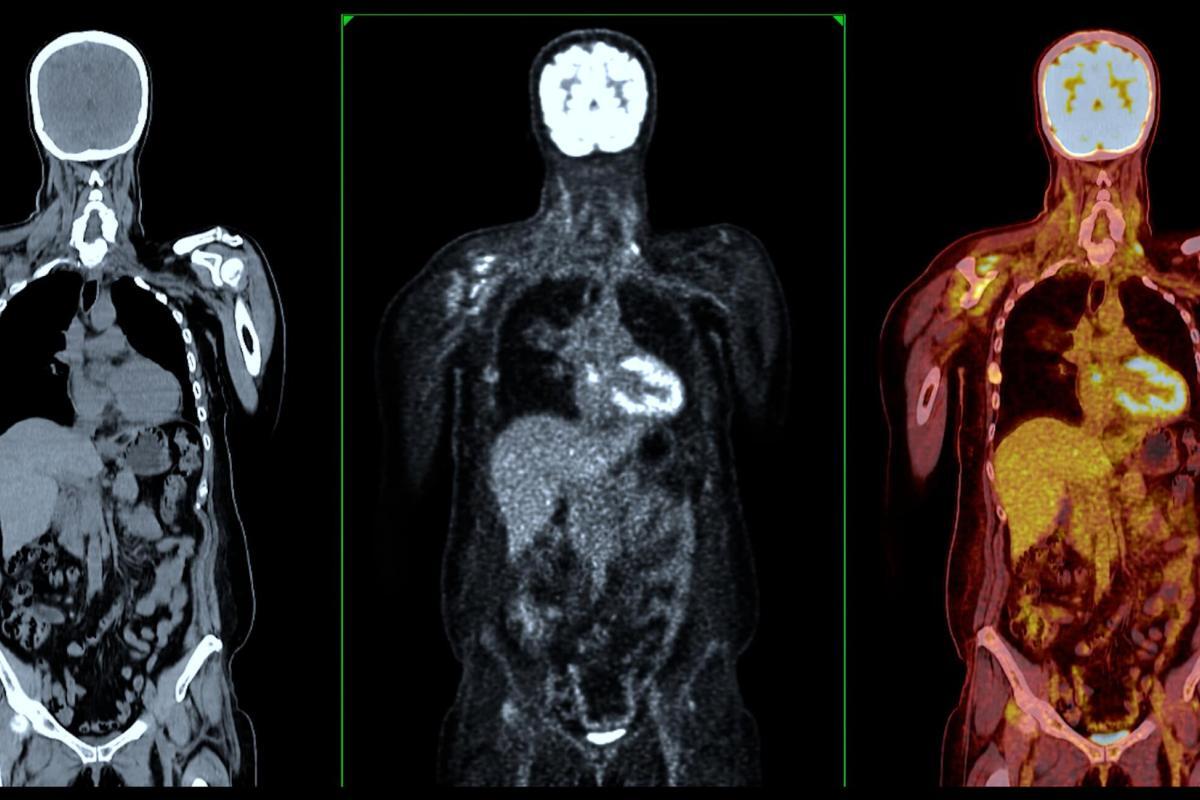

PET scanners utilise the unique properties of positron-emitting radiotracers. Detecting coincident gamma photons resulting from positron-electron annihilation allows for creating images with high resolution and sensitivity. This technique is particularly valuable for detecting metabolic changes in tissues, such as the increased glucose metabolism in cancer cells using FDG-PET. PET imaging is used in oncology, cardiology, and neurology, providing critical insights into myocardial perfusion and brain metabolism.

In the area of oncology, the impact of radiopharmaceutical diagnostics is profound. Cancer, a complex and multifaceted disease, requires precise diagnostic tools for its detection, staging, and the assessment of treatment efficacy. PET imaging, particularly with fluorodeoxyglucose (FDG), plays a central role in this regard. FDG, a glucose analogue, is preferentially taken up by cancer cells due to their higher metabolic rate compared to normal cells. This differential uptake allows for the detailed visualisation of primary and metastatic tumours across a wide range of cancers, including lymphoma, melanoma, and various solid tumours.

The use of FDG-PET imaging has transformed the landscape of cancer care. It provides clinicians with detailed information about tumour metabolism, which is invaluable in distinguishing between benign and malignant lesions, thus aiding in the initial diagnosis. Moreover, FDG-PET is instrumental in cancer staging, offering a whole-body overview that can detect even small metastatic deposits often missed by conventional imaging techniques. This comprehensive detection capability is crucial for determining the appropriate treatment strategy, which may range from surgical intervention to systemic therapies.

Furthermore, FDG-PET imaging is indispensable in monitoring the response to treatment. Changes in the metabolic activity of a tumour, as evidenced by FDG uptake, can indicate the effectiveness of the treatment regimen, often before changes in tumour size become apparent. This early feedback allows for timely modifications to therapy, potentially improving patient outcomes. Additionally, FDG-PET can help identify recurrence, guide follow-up care, and provide surveillance strategies for cancer survivors.